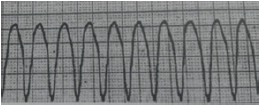

Foi realizado um exame de eletrocardiograma do paciente YHG, 66 anos, internado na Unidade de Terapia Intensiva Adulta. A figura abaixo representa o ritmo cardíaco deste paciente, é correto afirmar que trata de:

Taquicardia Ventricular

Fibrilação Ventricular

Extrassístole Ventricular

Fibrilação Atrial